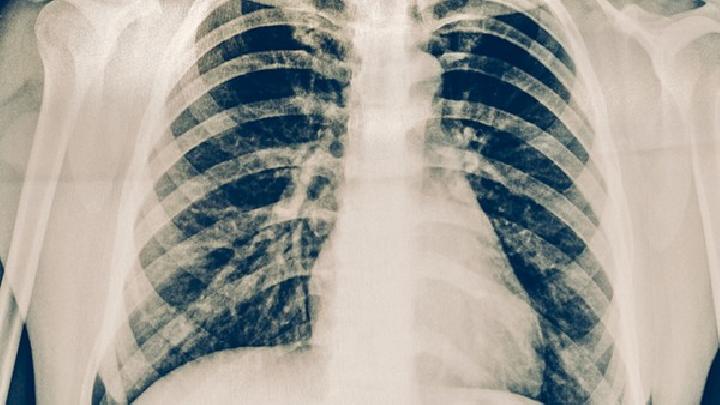

肺动脉高压发作该怎么办?肺动脉高压的发生带来的危害相当严重,因此我们要积极进行治疗,该疾病多在20~40岁间才逐渐出现气急、乏力、呼吸困难或有咯血、心悸、声音嘶哑等症状,那么,肺动脉高压发作该怎么办呢?

肺动脉高压指肺动脉压力升高超过一定界值的一种血流动力学和病理生理状态,可导致右心衰竭,可以是一种独立的疾病,也可以是并发症,还可以是综合征。那么实验室检查肺动脉高压的方法有哪些呢?

正常肺动脉高压指标是多少?肺动脉高压是各种原因引起的静息状态下右心导管测得的肺动脉平均压(≥25mmHg的一组临床病理生理综合征。静息状态下肺动脉收缩压和平均压分别超过30和20mmHg即为肺动脉高压。